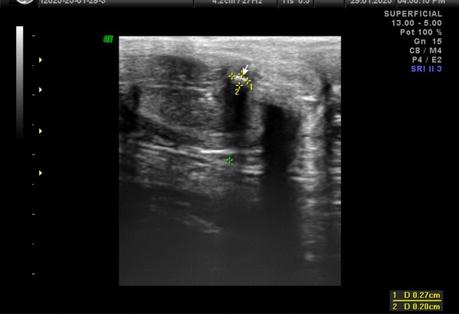

A nivel de base del pené, entre los cuerpos cavernoso y esponjoso en su porción central se observa la presencia de calcificación, que mide 2.2 mm. En tercio distal del pené, a nivel de cuerpos cavernosos con presencia de calcificación que mide 1.8 mm.

A NIVEL DE BASE Y TERCIO DISTAL DEL PENÉ, EN CUERPOS CAVERNOSOS CON PLACAS A RELACIÓN A ENFERMEDAD PEYRONIE.